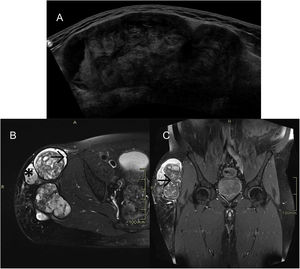

Case 3A 46-year-old male involved in a traffic accident ten years previously who had subsequently developed a tumour on the affected leg that had resolved spontaneously.

The patient was referred from another centre for suspicion of liposarcoma, and reported pain and a tumour in the same region as the accident, both of which had begun one year previously.

An ultrasound (Fig. 3A) and MRI (Fig. 3B) were performed, revealing an extensive lesion in the subcutaneous cellular tissue of the lateral aspect of the pelvis and root of the right thigh. The lesion was polylobulated and surrounded by a markedly hypointense thick capsule on all sequences. The content was highly heterogeneous, with a markedly hyperintense component on T1-weighted sequences.

A) Ultrasound and B) MRI: lesion in the subcutaneous cellular tissue of the lateral aspect of the pelvis and root of the right thigh, polylobulated, surrounded by a markedly hypointense thick capsule (→) on all sequences. The content is highly heterogeneous, with a hyperintense component (*) on the T1-weighted sequences. C) After intravenous contrast administration, central filiform enhancement is seen (→), with no peripheral or nodular enhancement.

After administration of paramagnetic contrast (Fig. 3C), central filiform enhancement was observed with no peripheral or nodular enhancement.

A complete surgical excision was carried out which confirmed the CEH diagnosis histologically and resulted in a favourable evolution.